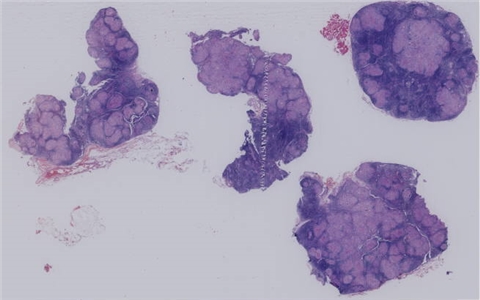

淋巴组织

增生性病变

淋巴结肉芽肿